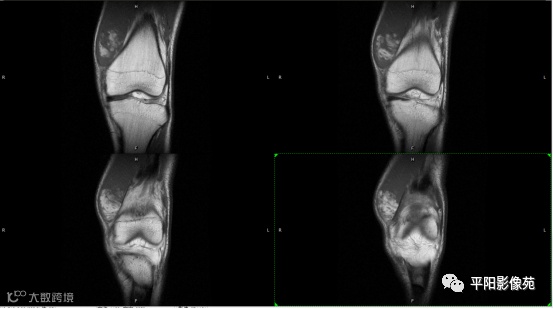

影像表现:

左膝关节股内侧肌内见多房样短T1长T2信号,内可见分隔,增强扫描明显强化,分隔未见明显强化,病灶局部与股骨远端分界不清。

MRI表现:好发于下肢, 较大病灶多为与肢体长轴一致的梭形, 边缘不清, 较小病灶呈类圆形, 边缘较清;②T1WI呈等或稍高信号, 病灶内部或边缘可见线条状或花边状高信号灶, 类似于皮下脂肪信号, T2WI上为明显高信号, 为本病特征性MRI表现;③病灶内静脉石及血管流空影为又一特征MRI表现;④GD-DTPA增强, 病灶明显强化, 其内低信号间隔无强化;⑤可见骨外形改变, 骨质增生及骨质吸收等表现。